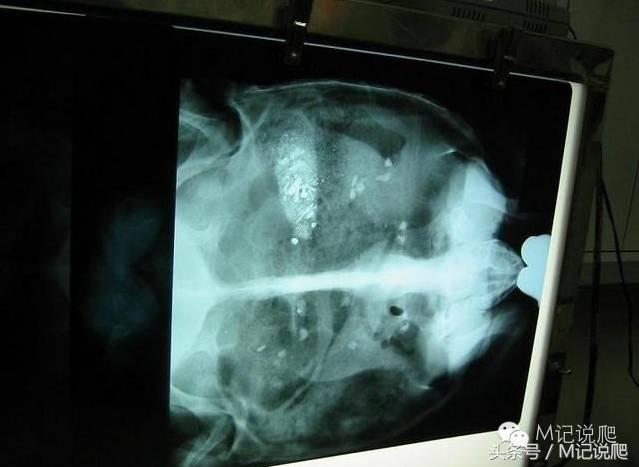

这是台湾一龟友(小宝)家的苏卡达,每月的例行检查龟状态及体重,发现这只苏卡达有些异常,而且俩周没排过大便,于是去宠物医院拍了X光,一看吓一跳,发现粪块跟一堆有的没的纠杂在一起...卡住过不去,仔细看好像有螺丝钉,针,跟不知名硬物。

颜色越白表示越硬……

不愧是主治医师,经验丰富,看完X光片就先准备这一根磁棒,用来吸取肠道内异物

刚看的X光片是手术当天拍的,好确认位置(肠道蠕动粪块会跑)

P.S.要各位回去看X光片,你有看到碗的破片吗??,我就是冲着它才来帮苏开刀的...一定要知道是啥

其实可能还没"完全"清完,不信回去再看一次X光片,嘿嘿